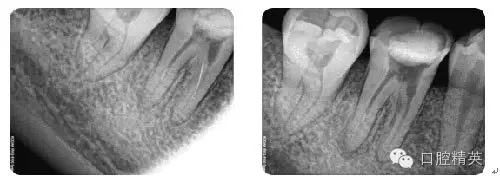

病例3:C型根管

病例4:根管再治療